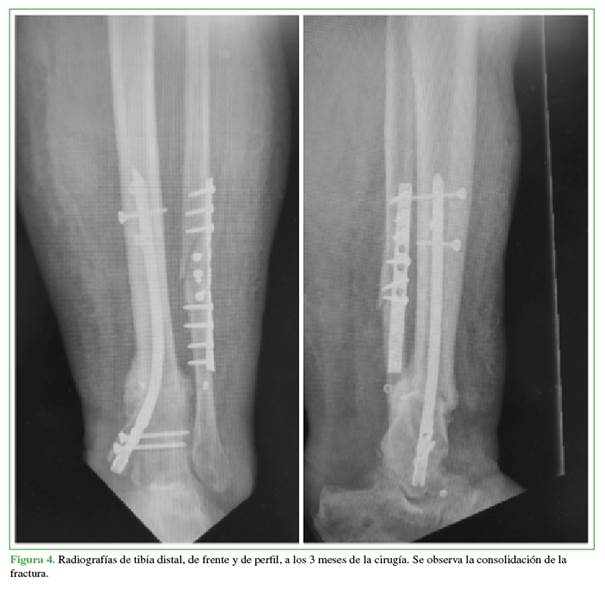

Se le realizaron radiografías (Figura 2) y reconstrucción tridimensional del tobillo (Figura 3), se diagnosticó una fractura de tibia distal OTA/AO42-A3.3 en la zona por donde transcurre la sutura del Endobutton®, y fue inmovilizado con una valva posterior de yeso.

En enero de 2023, concurrió a nuestra institución donde recibió tratamiento para la fractura de tibia con clavo endomedular de ingreso maleolar (Figura 4). Se decidió utilizar un clavo endomedular de ingreso maleolar a causa de la mala calidad de las partes blandas en la zona anterointerna de la pierna y el índice de masa corporal elevado.9 La evolución posquirúrgica fue favorable, se constató la consolidación de la fractura de tibia a los cuatro meses del procedimiento quirúrgico.